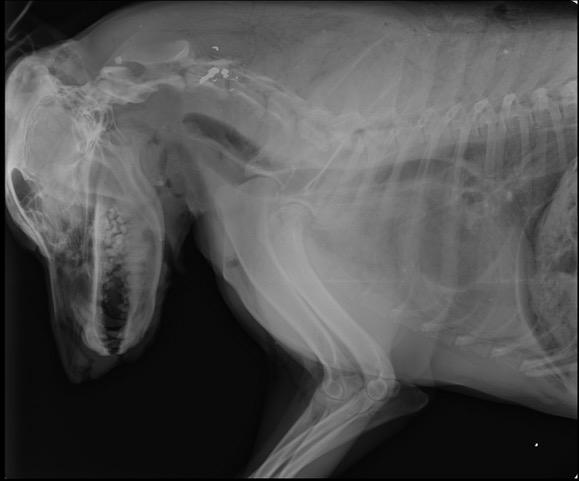

Το πυροβολημένο σκυλί μεταφέρθηκε στο κτηνιατρείο της Ειρήνης Μαυράκη «Vets4Life» όπου έγινε και η νεκροψία.

Το πυροβολημένο σκυλί μεταφέρθηκε στο κτηνιατρείο της Ειρήνης Μαυράκη «Vets4Life» όπου έγινε και η νεκροψία.

Τα σκάγια εντοπίστηκαν στον αυχένα του ζώου.

Τα σκάγια εντοπίστηκαν στον αυχένα του ζώου.

Οι άνθρωποι που την φρόντιζαν διεπίστωσαν ότι είχε τρύπα στο λαιμό και υπέθεσαν ότι είχε πυροβοληθεί. Το πρωί ο σκύλος μεταφέρθηκε σε κτηνιατρείο όπου μετά από εξέταση και ακτινογραφία διαπιστώθηκε ότι είχε έντονη αιμορραγία στο κεφάλι και τρύπα από σφαίρα στον τράχηλο.

Η ακτινογραφία έδειξε επίσης το βλήμα από πυροβόλο όπλο και τη σφαίρα να έχει καρφωθεί στην σπονδυλική στήλη. Ο θάνατος του σκύλου δεν ήταν ακαριαίος αλλά σίγουρα υπέφερε για αρκετή ώρα, μέχρι να καταλήξει. Αυτή τη φορά όμως ο δολοφόνος δεν σταμάτησε εδώ το έργο του...